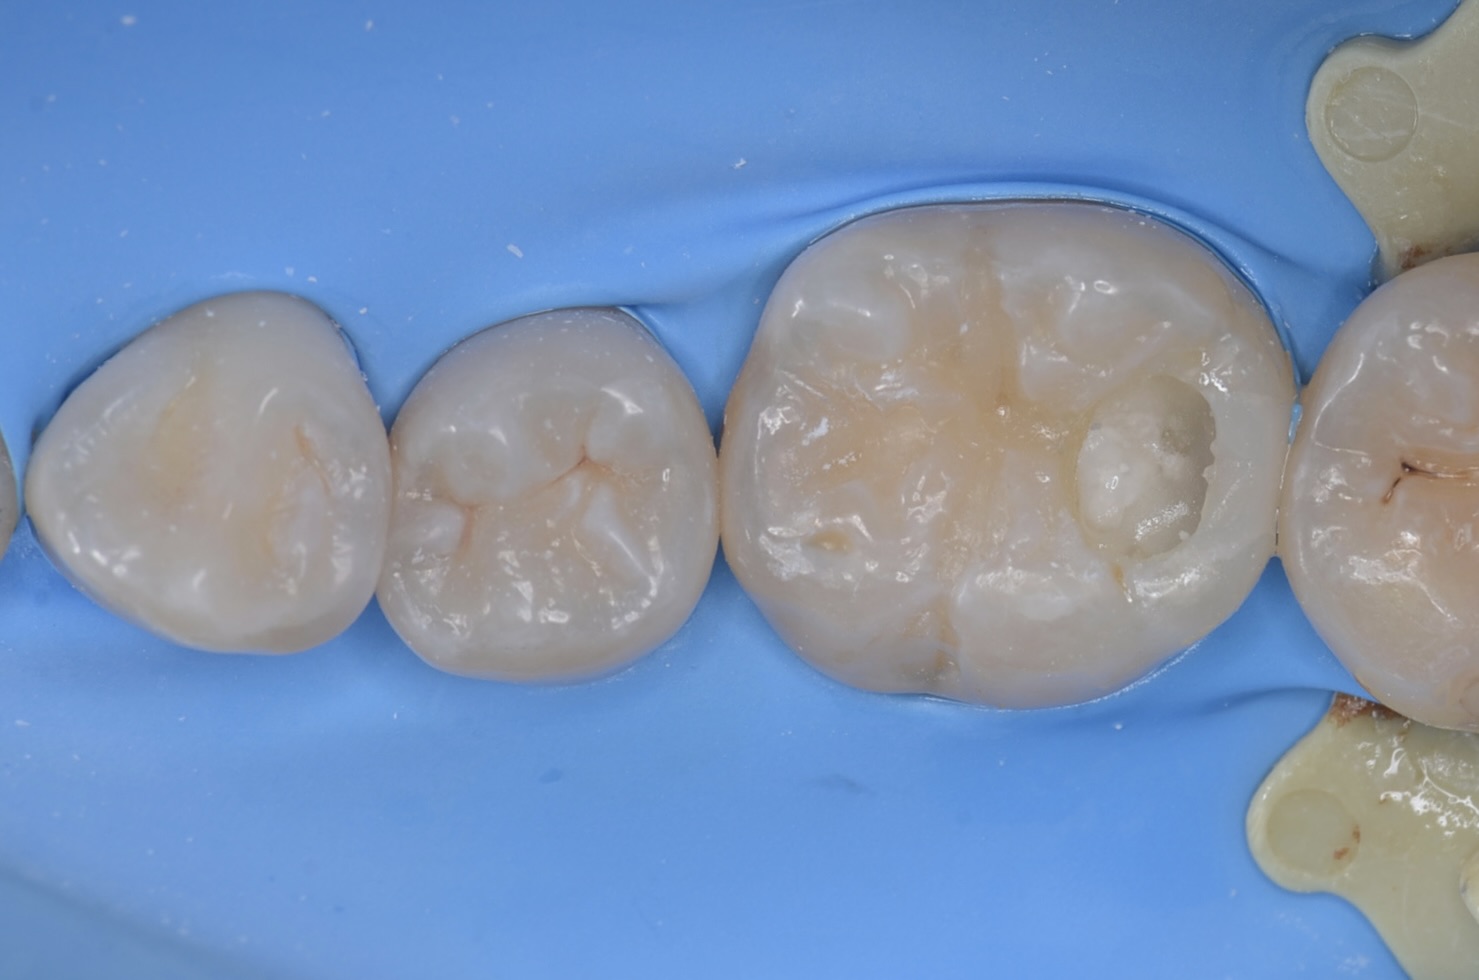

ダイレクトボンディング

天然歯の自然な形態を模倣してレジンを充填しました。 -